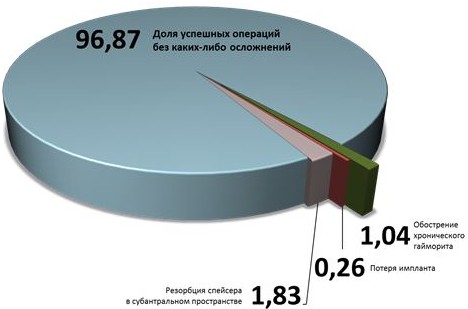

Из 383 операций синуслифтинга, проведенных мной в 2012-2013 гг., я наблюдал данное осложнение 4 раза, что дает частоту, примерно, в 1,04% — не так часто, как предполагают многие. Во всех случаях обострение гайморита развивалось на фоне длительно существующего (при этом, часто бессимптомного) хронического полириносинусита, что было достоверно установлено при ретроспективном анализе данных компьютерной томографии.

Наверное, это самое распространенное послеоперационное осложнение, с каким мне приходилось сталкиваться. За 2012-2013 гг., я наблюдал его в 1,83% случаев (7 случаев из 383 операций), причем у всех пациентов процесс протекал бессимптомно.

Частота осложнений синуслифтинга по результатам работы и 383 проведенным операциям за 2 года представлена на рисунке 62.